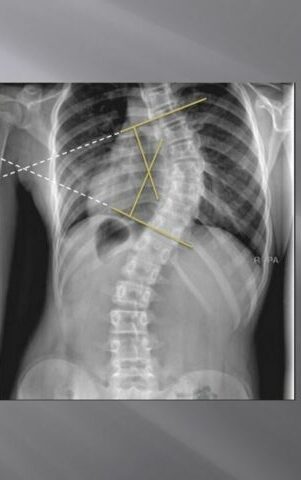

اعوجاج العمود الفقري الخلقي عند الأطفال اعوجاج العمود الفقري الخلقي هو نوع من أنواع اعوجاج العمود الفقري الذي يظهر قبل الولادة بسبب مشاكل في تكوّن الفقرات أثناء نمو الجنين في الرحم. في هذا المقال،

متابعة اعوجاج العمود الفقري لدى الأطفال بدون أشعة سينية حل مبتكر لمتابعة حالة اعوجاج العمود الفقري لدى الأطفال بدون أشعة سينية إذا كنت من الآباء الذين يعانون من مشكلة الجنف (اعوجاج العمود الفقري) لدى

اعوجاج العمود الفقري عند الكبار: الأسباب وأفضل طرق العلاج اعوجاج العمود الفقري هو انحناء غير طبيعي في العمود الفقري على شكل حرف S أو C، وقد يؤثر على شكل الجسم والحركة. وعلى الرغم من